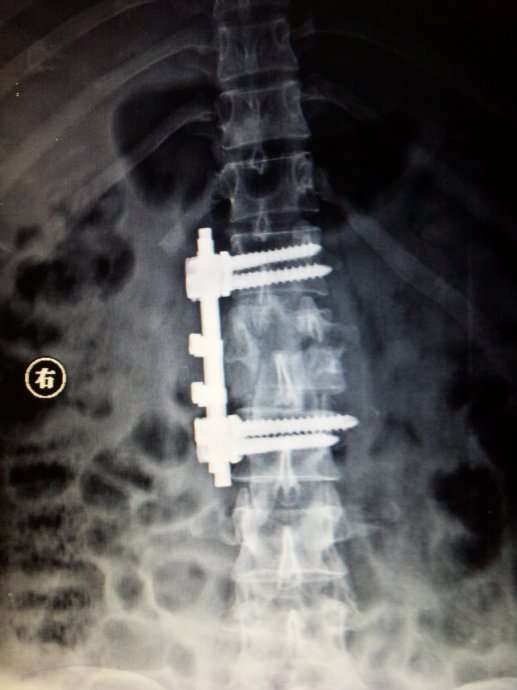

在全麻下行右侧前方入路,第一腰椎椎体次全切除减压,取同侧髂骨植骨融合前路钉棒系统内固定术。术后患者清醒,安返病房,双下肢感觉运动无异常。目前已能自主排尿。这是手术后X光片: